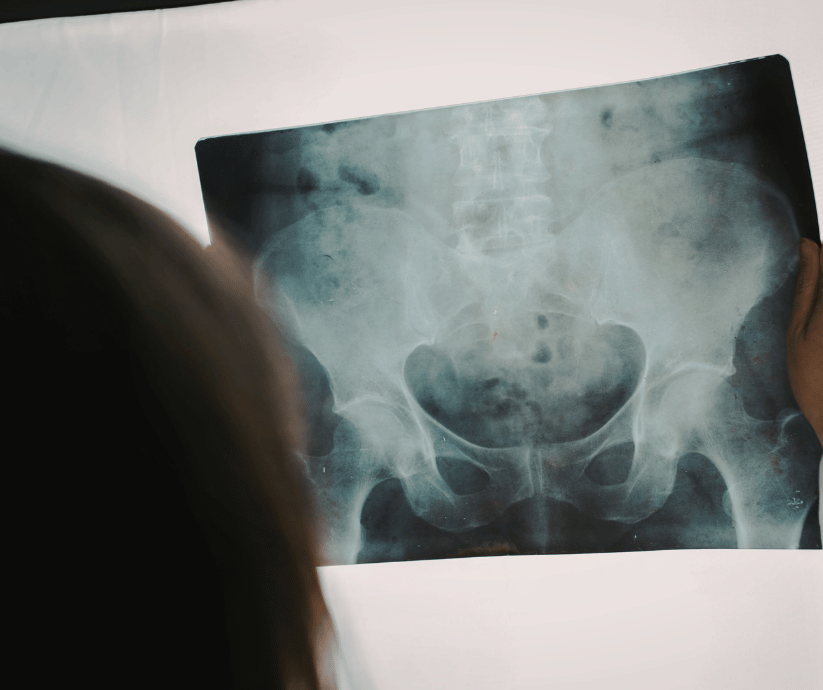

Broken bones and fractures are among the most common injuries in personal injury cases and can range from relatively minor to life-altering. While some fractures heal with rest and immobilization, others require surgery, long-term rehabilitation, or result in permanent limitations. Fractures commonly occur in car accidents, truck crashes, motorcycle and bicycle accidents, pedestrian incidents, falls, and workplace injuries. The force involved in these accidents often leads to broken arms, legs, hips, ribs, wrists, ankles, or more complex injuries such as pelvic or compound fractures. A broken bone or fracture injury claim allows an injured person to seek compensation when the injury is caused by another party's negligence. Because the type and severity of a fracture significantly affect recovery time and long-term impact, understanding how fracture claims work is essential to pursuing fair compensation.

Fractures can occur in nearly any part of the body and vary widely in severity. Some of the most common fracture injuries include arm fractures, leg fractures, wrist and hand fractures, ankle and foot fractures, and collarbone fractures. These injuries often limit mobility and interfere with daily activities and work. More serious fractures include hip fractures, pelvic fractures, rib fractures, and compound fractures, where the bone breaks through the skin. These injuries often require surgery, hospitalization, and extensive rehabilitation, particularly in older adults or high-impact accidents. Some fractures heal cleanly, while others result in complications such as improper healing, chronic pain, reduced range of motion, or nerve damage. The specific type of fracture plays a major role in the value and complexity of a claim.

Proper documentation is critical in fracture injury claims. Immediate medical treatment helps establish the existence and severity of the injury. Medical records may include X-rays, CT scans, surgical reports, orthopedic evaluations, and physical therapy records. Following all treatment recommendations and attending follow-up appointments strengthens a claim. Personal documentation describing pain levels, mobility limitations, and daily challenges can further support medical evidence and demonstrate how the fracture affects everyday life.